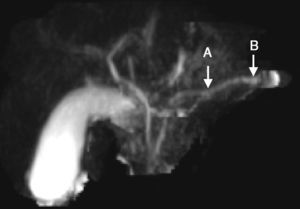

Presentamos el caso de un paciente que ingresa a los 8 años de edad al Hospital Pablo Tobón Uribe, por cuadro de dolor abdominal localizado en el epigastrio, náuseas y vómito. En adecuado estado nutricional, con dolor a la palpación del epigastrio, sin otros signos patológicos. Antecedente de un episodio previo de pancreatitis aguda a los 7 años y antecedente familiar de hermano con historia de pancreatitis aguda, sin otros datos relevantes. El cuadro de ingreso fue indicativo de pancreatitis aguda no complicada, con enzimas pancreáticas elevadas (amilasa 1,359; lipasa 3,098) (tabla 1). La resonancia magnética del páncreas realizada revela dilatación irregular del conducto de Wirsung (fig. 1). Teniendo en cuenta los antecedentes y los hallazgos bioquímicos y radiológicos, se inicia abordaje diagnóstico para pancreatitis crónica, descartándose otras causas, como hipercalcemia y pancreatitis autoinmune, con cuantificación de inmunoglobulina G subclase 4, que se encontró dentro de parámetros normales. Se realizaron estudios moleculares que incluyeron 60 mutaciones para el CFTR las cuales fueron negativas, reportando solo la presencia de la mutación N34S del gen SPINK 1, en el exón 3. En un año de seguimiento en la institución, el paciente presentó un nuevo cuadro de pancreatitis aguda no complicada y no ha presentado evidencia de insuficiencia endocrina o exocrina.

| Colangiorresonancia Simple y contrastada | Páncreas con arrosariamiento del conducto de Wirsung, parénquima normal. Sin anomalías congénitas bilio-pancreáticas ni litiasis | |

El paciente descrito ha presentado 3 cuadros de pancreatitis aguda con periodos intercríticos asintomáticos, dilatación irregular del conducto de Wirsung evidenciada por imagen e identificación de la mutación N34S del gen SPINK1. Este gen mutado se ha asociado a pancreatitis aguda recurrente, crónica hereditaria, alcohólica, calcificante tropical e idiopática3. También se ha asociado a mayor tasa de litiasis pancreática, seudoquistes y calcificaciones4. De igual forma, se ha visto en un pequeño porcentaje de los controles asintomáticos y en otras patologías pancreáticas, lo cual indica que estas mutaciones, más que causales, son factores modificadores de la enfermedad. En este caso no se encontró otra causa atribuible más que la alteración del SPINK1 con la limitación que no se estudiaron otros genes, como CTRC, y otros exones del PRSS1.

La presentación clínica más frecuente es el inicio a edades tempranas, alrededor de los 10 años, con cuadros intermitentes de náuseas y vómitos, donde el dolor abdominal puede no ser el síntoma principal, con progresión lenta hacia la insuficiencia pancreática y el compromiso de la función endocrina, que puede ocurrir en edades más avanzadas, con evidencia radiológica de cambios estructurales (dilatación irregular de los conductos pancreáticos, atrofia, calcificación glandular, alteraciones en la grasa peripancreática)2,3,5,6.